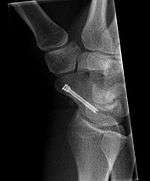

Fracture

Fractures of the scaphoid are the most common of the carpal bone injuries, because of its connections with the two rows of carpal bones.[1] :177

The scaphoid can be slow to heal because of the limited circulation to the bone. Fractures of the scaphoid must be recognized and treated quickly, as prompt treatment by immobilization or surgical fixation increases the likelihood of the bone healing in anatomic alignment, thus avoiding mal-union or non-union. Delays may compromise healing. Failure of the fracture to heal ("non-union") will lead to post-traumatic osteoarthritis of the carpus.[1] :189 One reason for this is because of the "tenuous" blood supply to the proximal segment.[2] Even rapidly immobilized fractures may require surgical treatment, including use of a headless compression screw such as the Herbert screw to bind the two halves together.

Healing of the fracture with a non-anatomic deformity (frequently, a volar flexed "humpback") can also lead to post-traumatic arthritis. Non-unions can result in loss of blood supply to the proximal pole, which can result in avascular necrosis of the proximal segment.